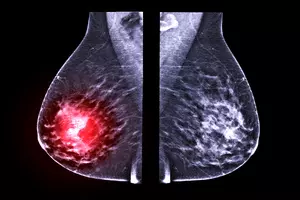

유방암은 여성에게 가장 흔한 암이며, 조기에 발견하면 치료 성공률이 높아집니다. 유방암 검사는 조기에 발견하기 위한 필수적인 검사이며, 여성의 연령, 건강 상태, 가족력 등에 따라 검사 시기와 권장되는 검사 종류가 다릅니다.

유방암 검사는 유방암을 진단하기 위한 중요한 검사이며, 유방 촬영술, 유방 초음파 검사, MRI, CT, 조직검사가 있습니다. MRI와 CT 검사는 금식이 필요하며, 검사 종류에 따라 금식 시간과 방식이 다릅니다. 유방 촬영술, 유방 초음파 검사는 금식이 필요하지 않습니다.